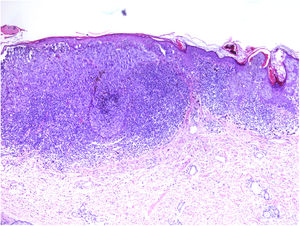

Linfocitos infiltrantes de tumorLa presencia de infiltrado linfocítico se interpreta como la respuesta del huésped frente al tumor. En la literatura se ha relacionado la intensidad del infiltrado con el pronóstico del paciente35.

Se clasifica como «ausente» cuando no se identifica infiltrado o este existe pero no está en contacto con el tumor; «intenso» cuando el infiltrado infiltra completamente la base del tumor (fig. 1) o infiltra difusamente el tumor (fig. 2); por último, es «no intenso» cuando el infiltrado está en el tumor solo de forma focal o afecta a la base del tumor pero no en toda su longitud.

Además, se debe especificar si es intratumoral, peritumoral o ambos.